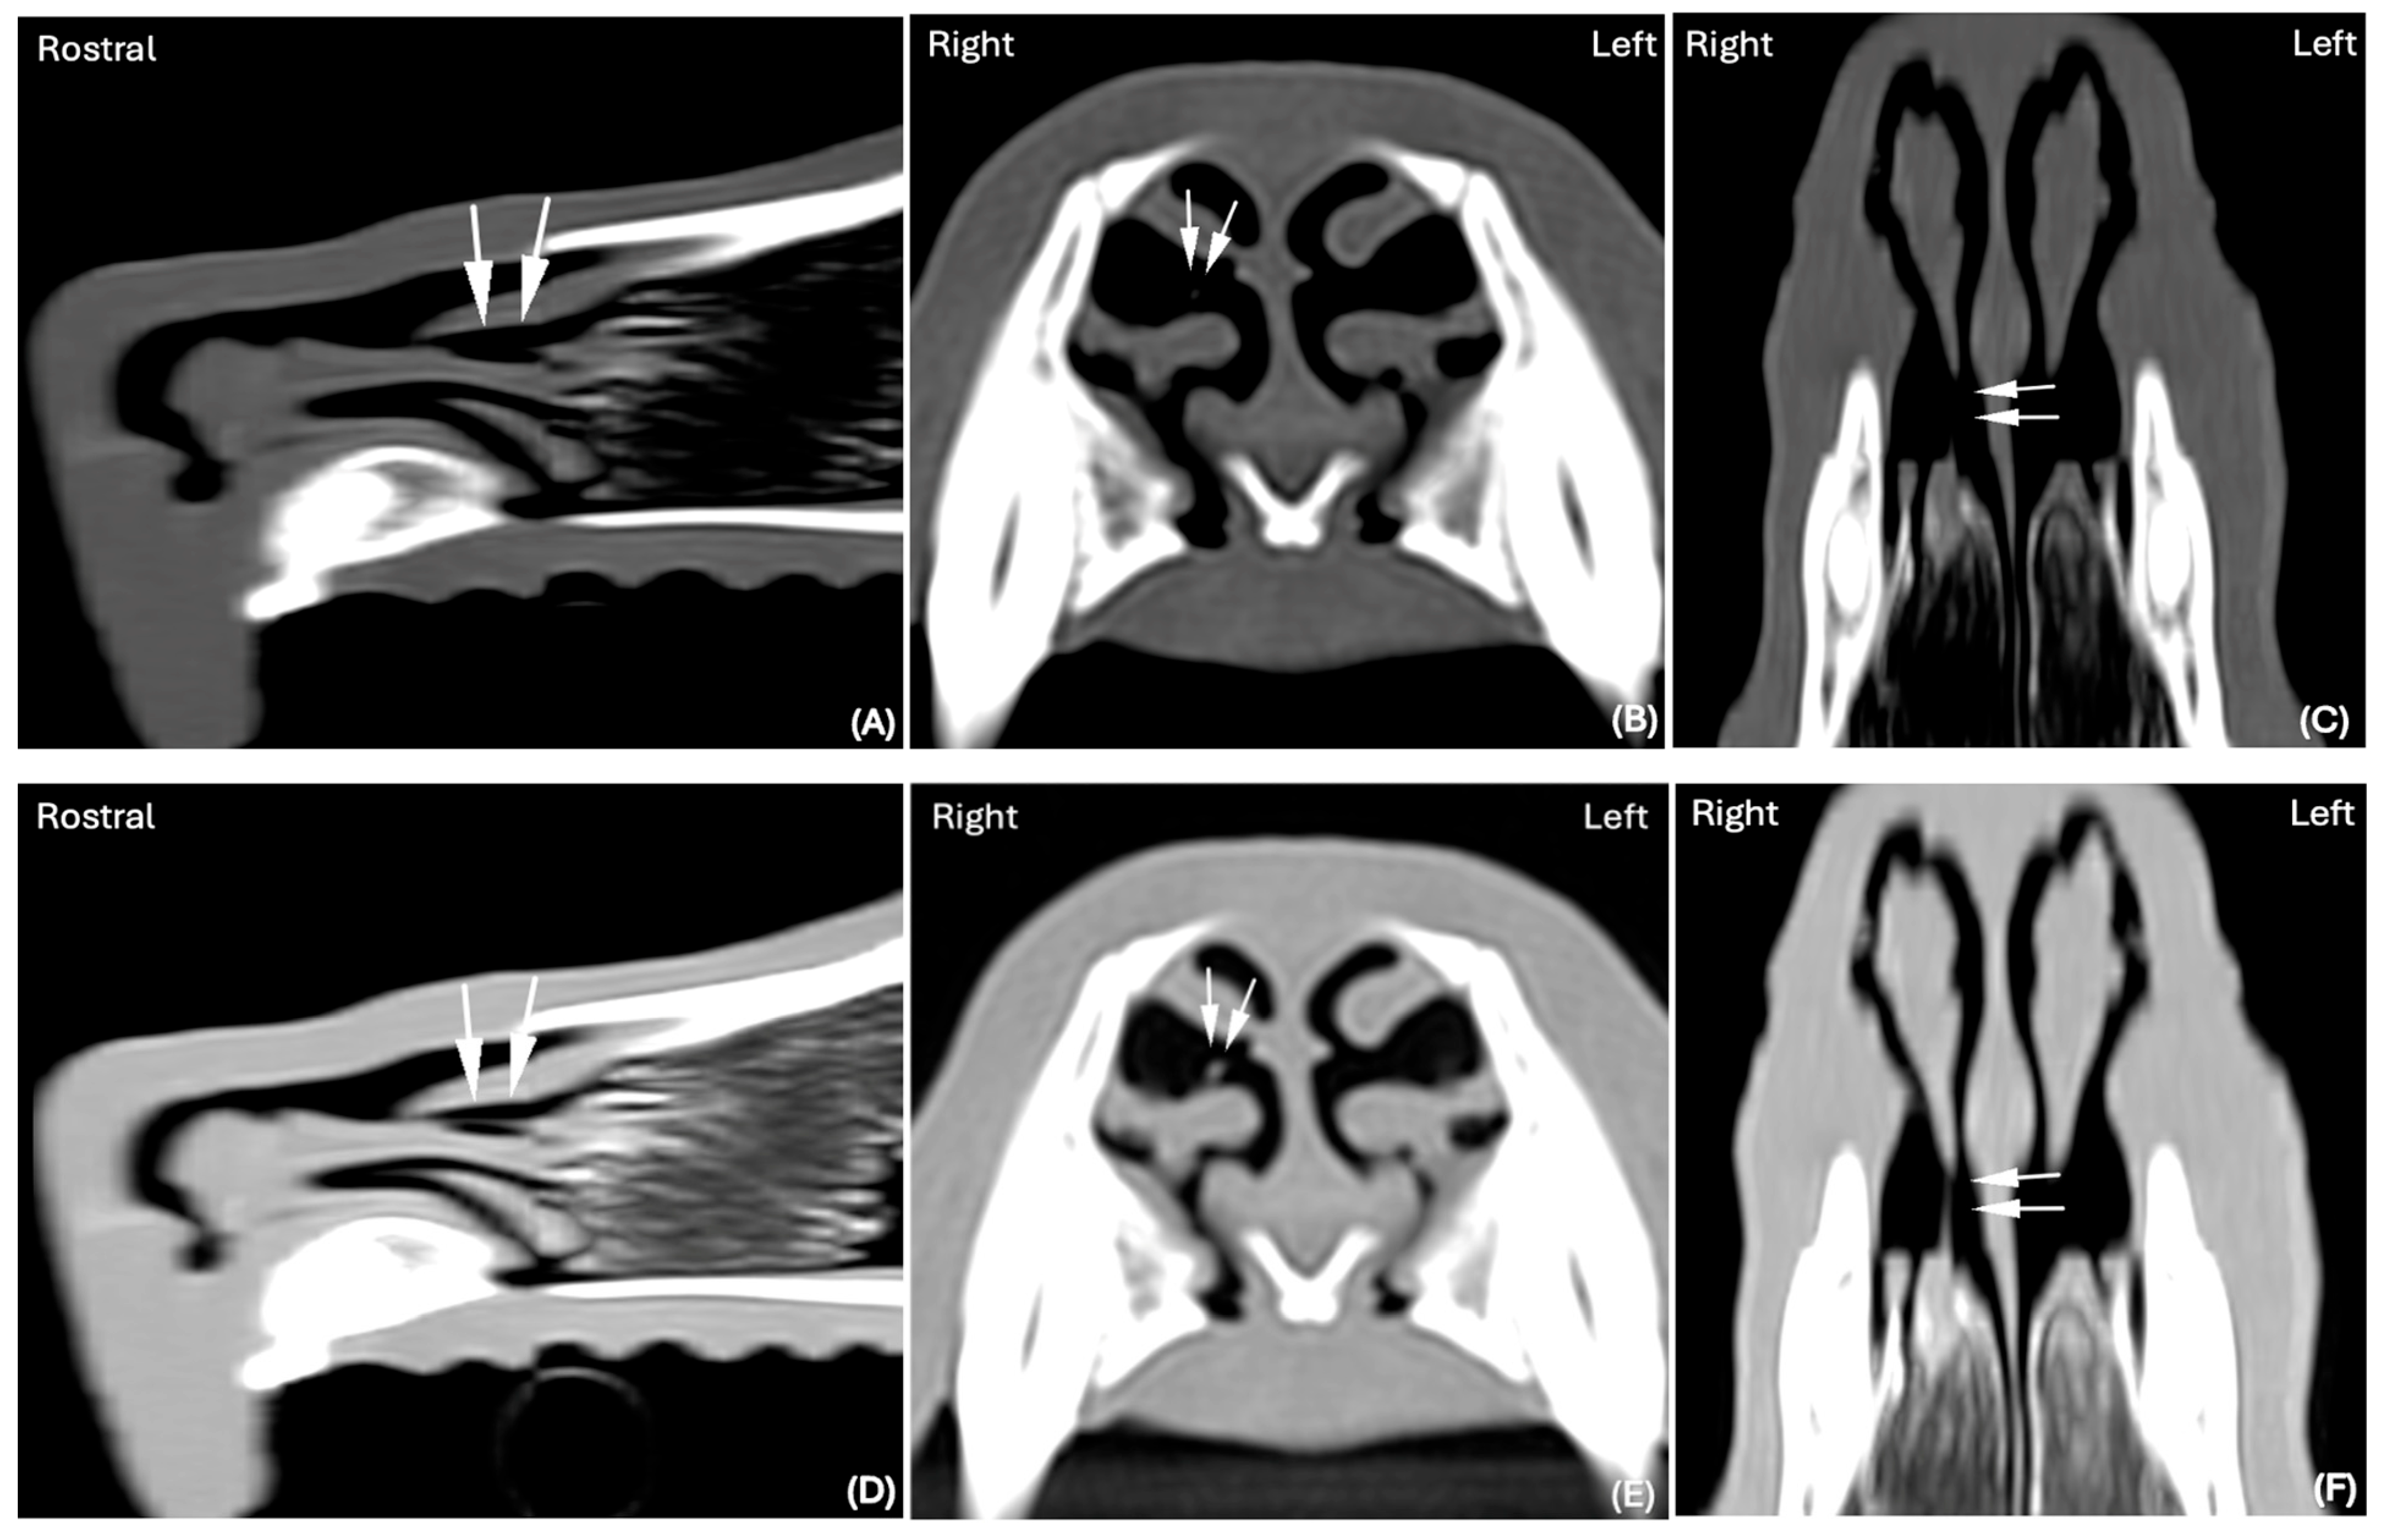

In both the LW and BW, the shape of the FBs was elongated in 14 cases (30%), elongated and splitting in two halves in 1 case (2%) and elongated with branching in another case (2%). An example of an elongated nasal FB visible in the BW and LW and detected by both reviewers is visible in Figure 1.

Figure 1. CT images in (A) Sagittal and (B) Transverse planar reconstruction, displayed in BW (WL 300 HU, WW 1500 HU); scale (DPI 144 × 144). CT images in (C) Sagittal and (D) Transverse planar reconstruction displayed in LW (WL −500 HU, WW 1400 HU); scale (DPI 144 × 144) of the same dog (Hungarian Vizsla, 2 years old, ME) of the nasal cavity. An elongated, thick hypoattenuating structure was clearly visualized in BW and LW (white arrows) lodged in the right nasal cavity. A long wooden stick was successfully retrieved via rhinoscopy.